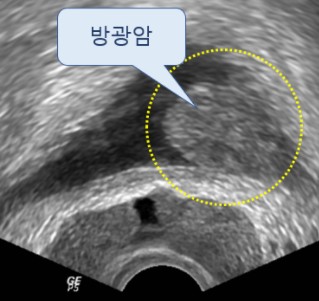

혈뇨는 소변에 피가 섞여 나오는 증상으로, 상식적으로 신장이나 방광에 문제가 있다는 신호일 수 있으기 때문에 미리 체크를 받아보는 것이 좋아요. 전립선암도 혈뇨의 흔한 원인인데요. 전립선의 암세포는 전립선으로 출혈을 일으켜 혈뇨를 일으킬 수 있지만, 혈뇨는 전립선암의 흔한 증상일 뿐 아니라 요로감염이나 전립선의 거시적 문제와 같은 다른 일시적인 원인으로도 확인될 수 있어요.